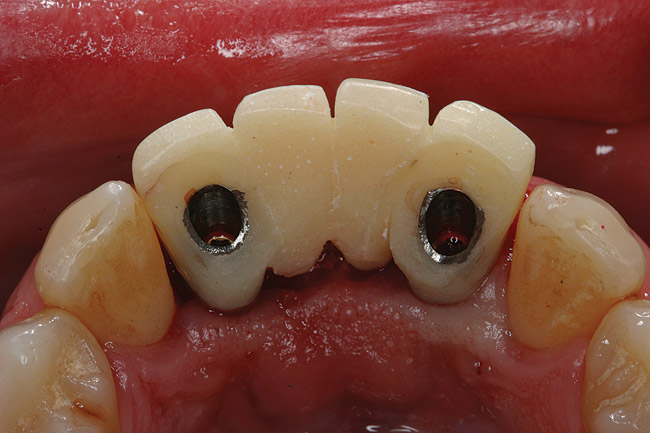

Figure 4  Tapered implants with conical transgingival abutments and temporary cylinders in place.

Figure 4

The patient was given postoperative instructions and advised to maintain a soft diet for 6 to 8 weeks to protect the implants. The patient was followed weekly for the first 3 weeks and monthly thereafter. After 4 months of healing, the provisional restoration was removed and the soft tissues were examined. Mature, keratinized gingival tissues were present facially, lingually, and interproximally. Nonkeratinized tissue could be seen at the tissue surfaces of the ovate pontics and in the intrasulcular regions of the implant abutment units. No clinical probing depths beyond 1 mm were found adjacent to the abutments. The healed tissue represented an acceptable clinical result especially in light of the gap that had been present at the time of implant placement (Figure 7A and Figure 7B). Final impressions were made, and the permanent ceramo-metal screw-retained prosthesis was placed within 8 weeks (Figure 8).